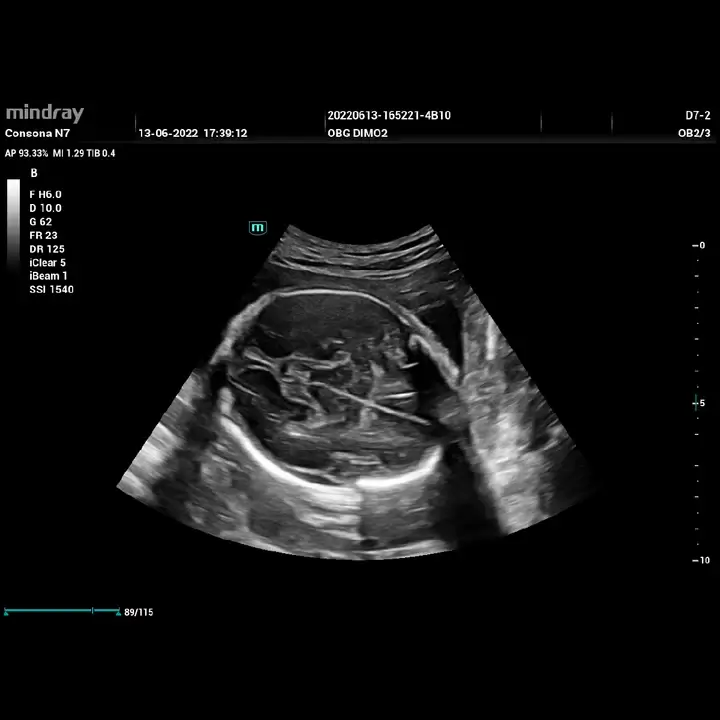

Ultrasonido Consona N7 Mindray: precisión diagnóstica y eficiencia clínica

El ultrasonido Consona N7 de Mindray es una solución de imagenología avanzada diseñada para médicos especialistas, clínicas y hospitales que buscan alta calidad de imagen, flujos de trabajo optimizados y un equipo confiable para el diagnóstico diario.

Ginecología y obstetricia

- Plataforma de imagen avanzada Mindray para una mayor nitidez y definición

- Pantalla Full HD de gran formato, ideal para una lectura precisa

- Tecnologías de reducción de ruido y mejora de contraste

- Doppler color, Power Doppler y espectral de alta sensibilidad

Estas características permiten obtener imágenes confiables incluso en estudios complejos o pacientes difíciles.